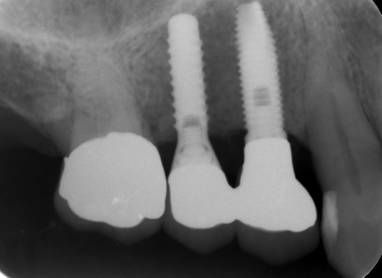

ストローマンインプラントとスプラインインプラント

術前

ストローマンインプラントとスプラインインプラントが隣り合わせに埋入されています.このころストローマンからスプラインに変えています。変えた理由は前歯部の審美性に優れていること、アバットメントの自由度があること、抜歯後すぐに埋入できるなどでした。

6年後。犬歯にコンポジット充填。第一大臼歯はメタルボンドになりました

8年後ほとんど変化がありません